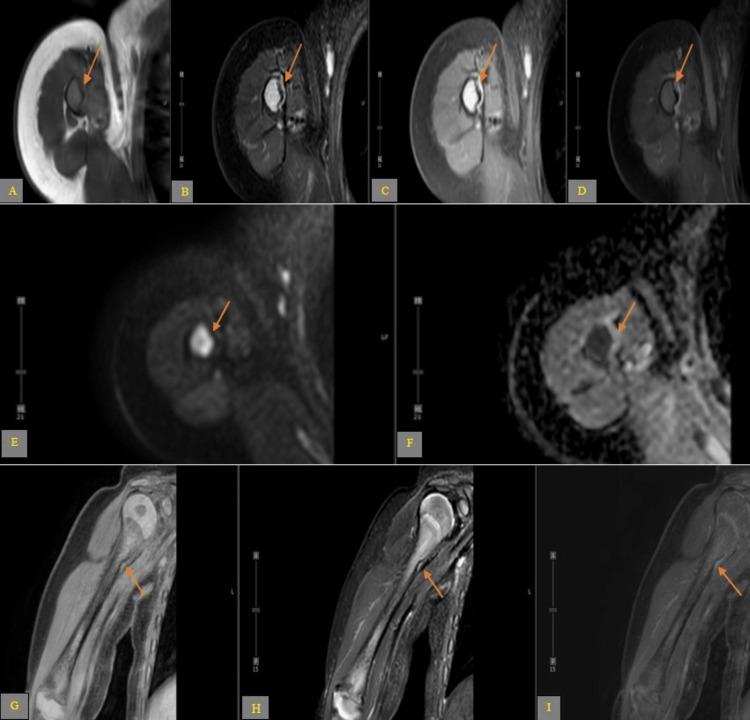

When a medical image is requested for a particular indication, and a bony lesion is seen in a child, it causes anxiety to caregivers, unnecessary imaging costs, and unneeded biopsy. We present a complicated course of a five-month-old child who initially presented to the emergency room for prolonged cough and underwent a chest x-ray demonstrating clear lungs; however, a right humerus lytic lesion was identified. The child underwent multiple diagnostic imaging work-ups, which revealed a normal bone variation. This case report will describe a benign upper humeral notch variant with the goal to familiarize radiologists and clinicians with this entity and encourage them to obtain contralateral view radiographs to confirm bilaterality, prevent unnecessary advanced imaging as well added cost and anxiety to the parents.

当因特定指征要求进行医学影像检查,且在儿童中发现骨病变时,会给护理人员带来焦虑、造成不必要的影像检查费用以及不必要的活检。我们介绍一名五个月大儿童的复杂病例,该儿童最初因长期咳嗽前往急诊室,胸部X光显示肺部清晰;然而,发现右肱骨有溶骨性病变。该儿童接受了多项诊断性影像检查,结果显示为正常的骨骼变异。本病例报告将描述一种良性的肱骨上端切迹变异,目的是让放射科医生和临床医生熟悉这一实体,并鼓励他们获取对侧的X光片以确认双侧情况,防止不必要的高级影像检查以及给家长增加费用和焦虑。